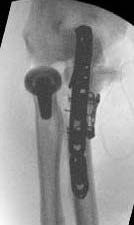

Medial approach and buttress plate with LCL repair

buttress plate

Universal posterior approach with radial head replacement and medial approach with medial buttress plate